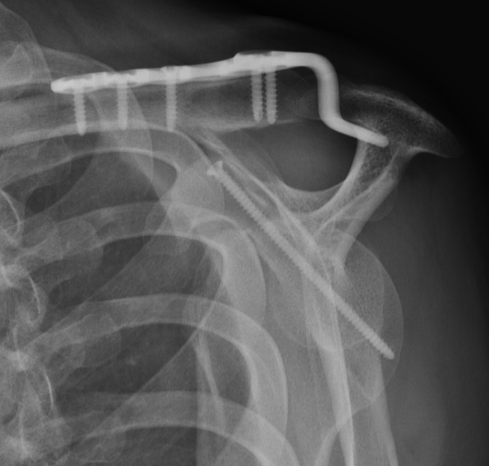

Type IA: Anterior glenoid rim fracture

Xray / CT